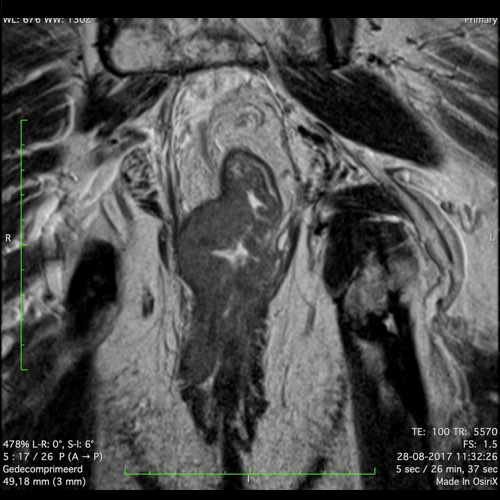

Hình ảnh

Các hình ảnh được cung cấp cho thấy ung thư biểu mô tế bào nhẫn với tình trạng dày lan tỏa thành trực tràng, hình ảnh bia bắn điển hình, và sự xâm lấn mỡ mạc treo trực tràng.